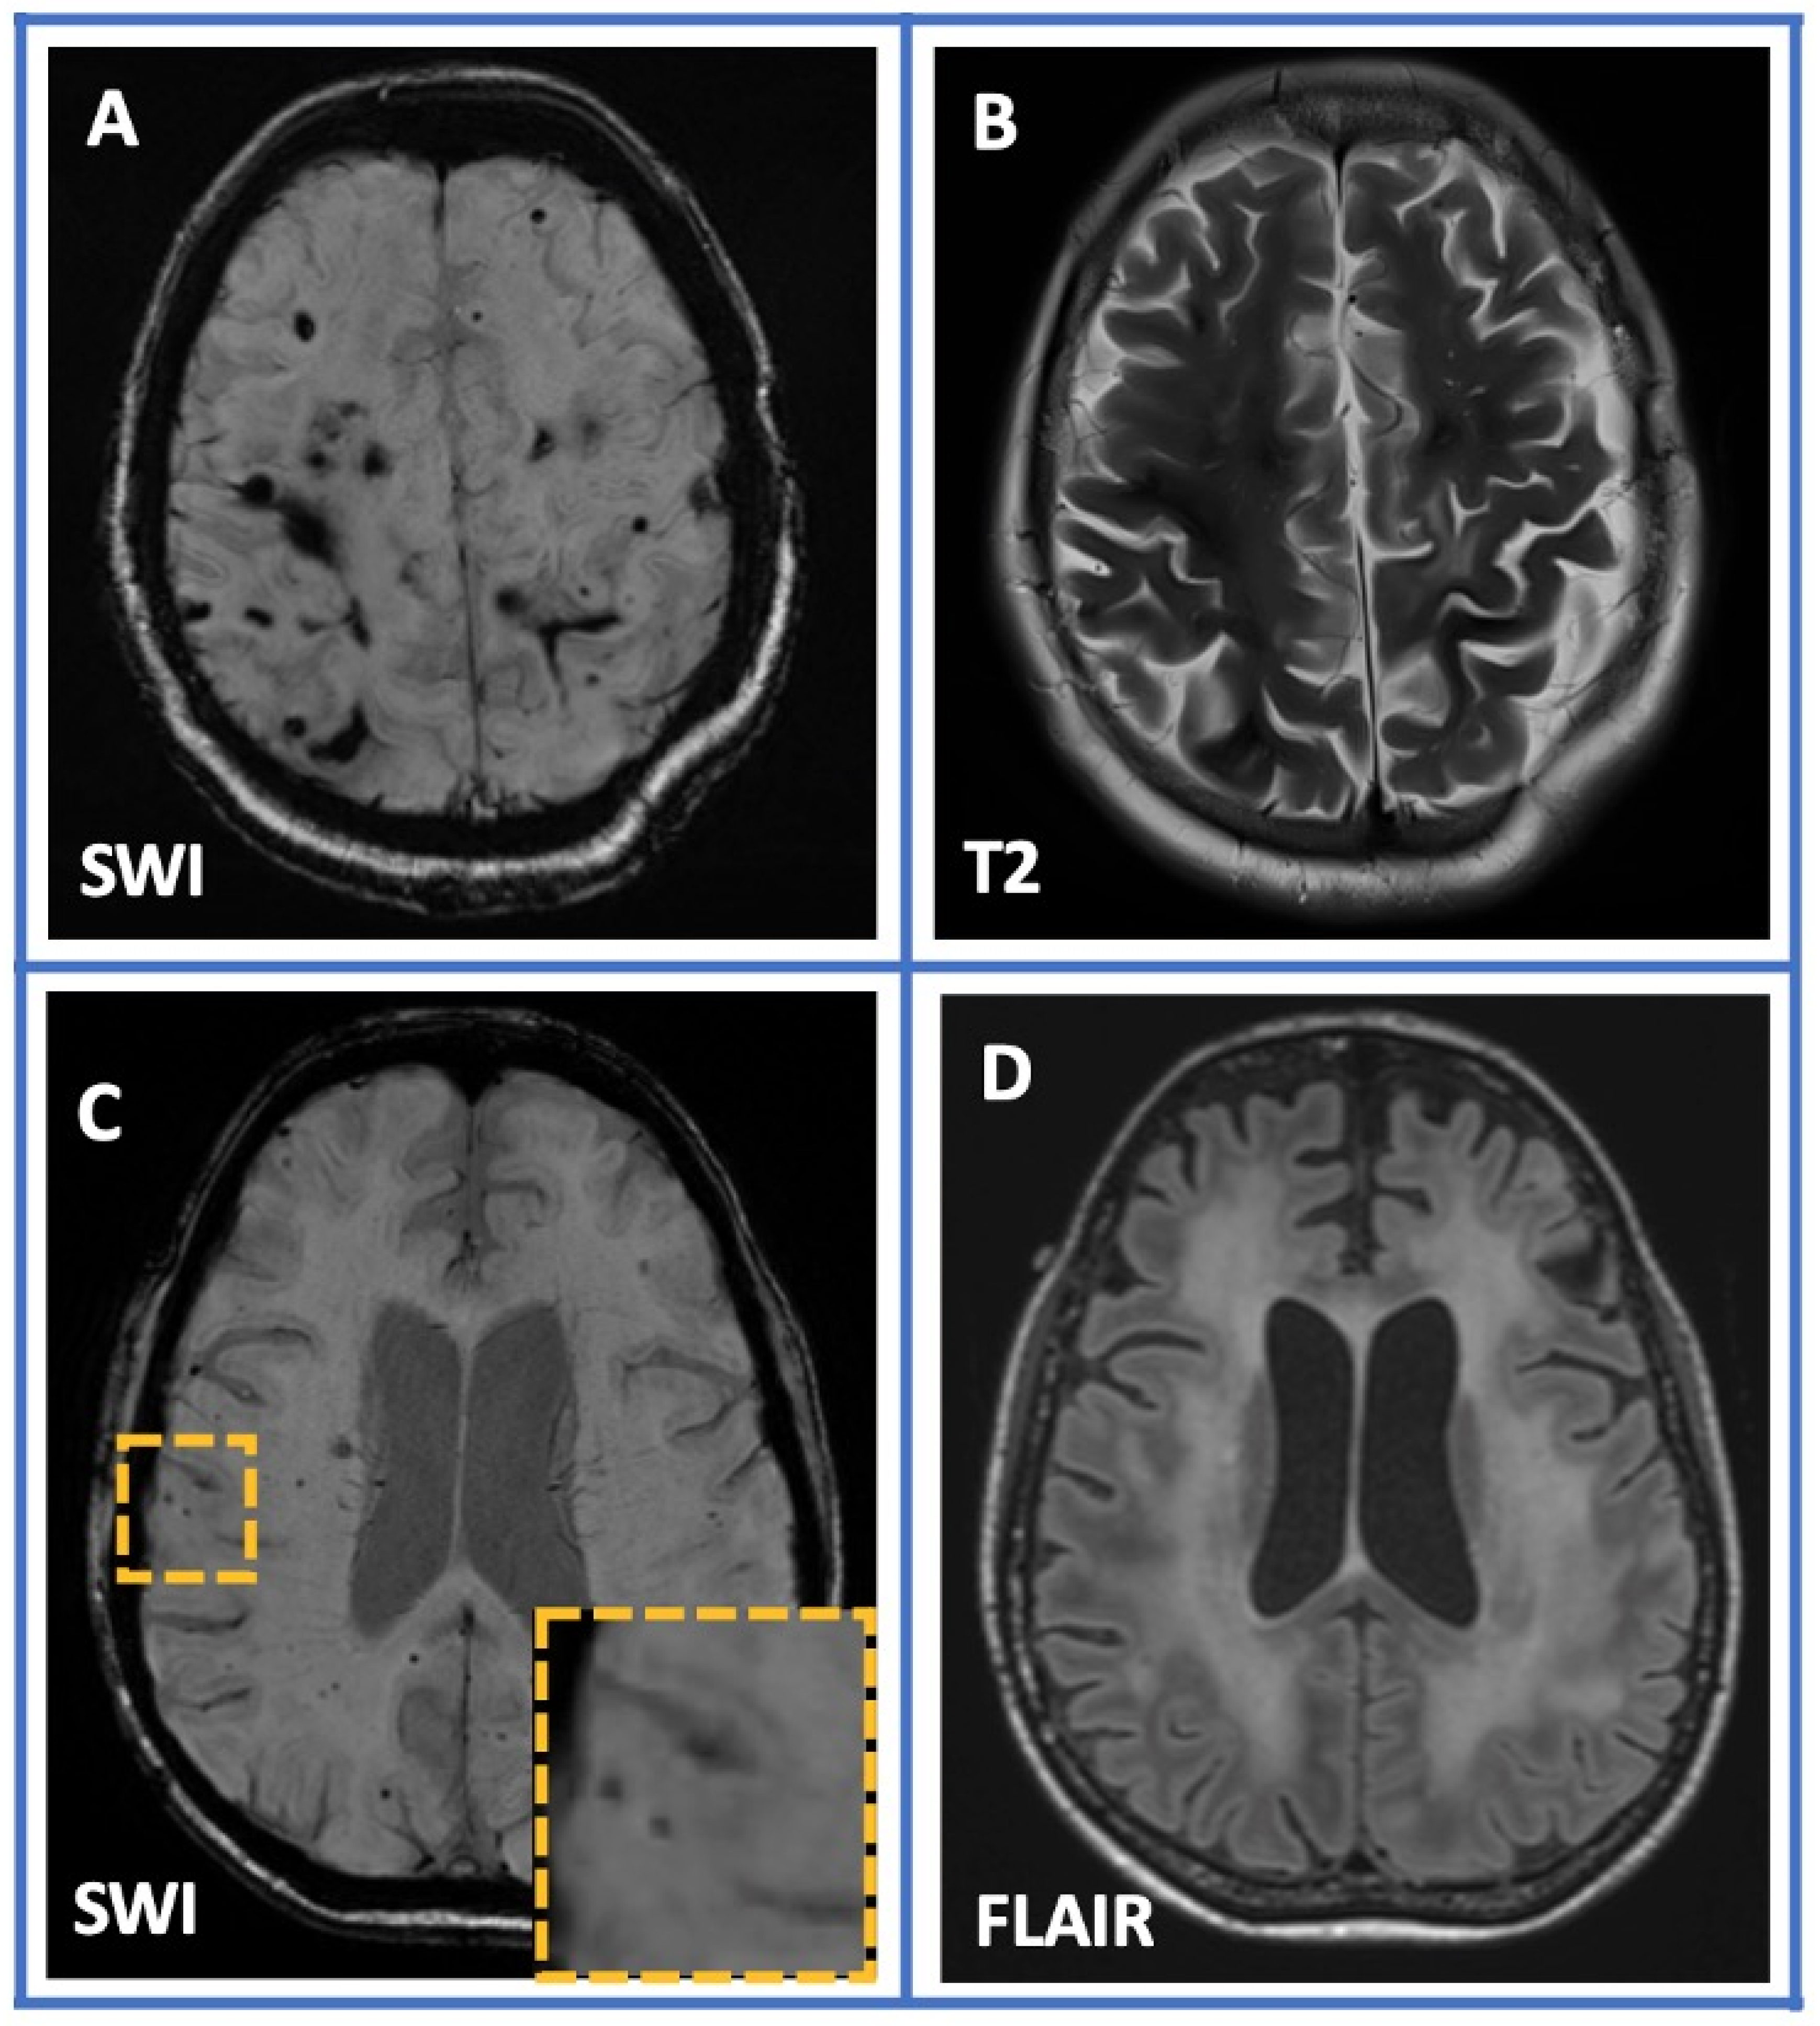

- Theodorou, A.; Chondrogianni, M.; Bakola, E.; Kaloudi, G.; Foska, A.; Michalakakou, S.; Melanis, K.; Paraskevas, G.P.; Tsivgoulis, G. Cortical Superficial Siderosis and Transient Focal Neurological Episode Preceding Lobar Hemorrhage in Cerebral Amyloid Angiopathy. Stroke 2023, 54, e48–e51. [Google Scholar] [CrossRef]